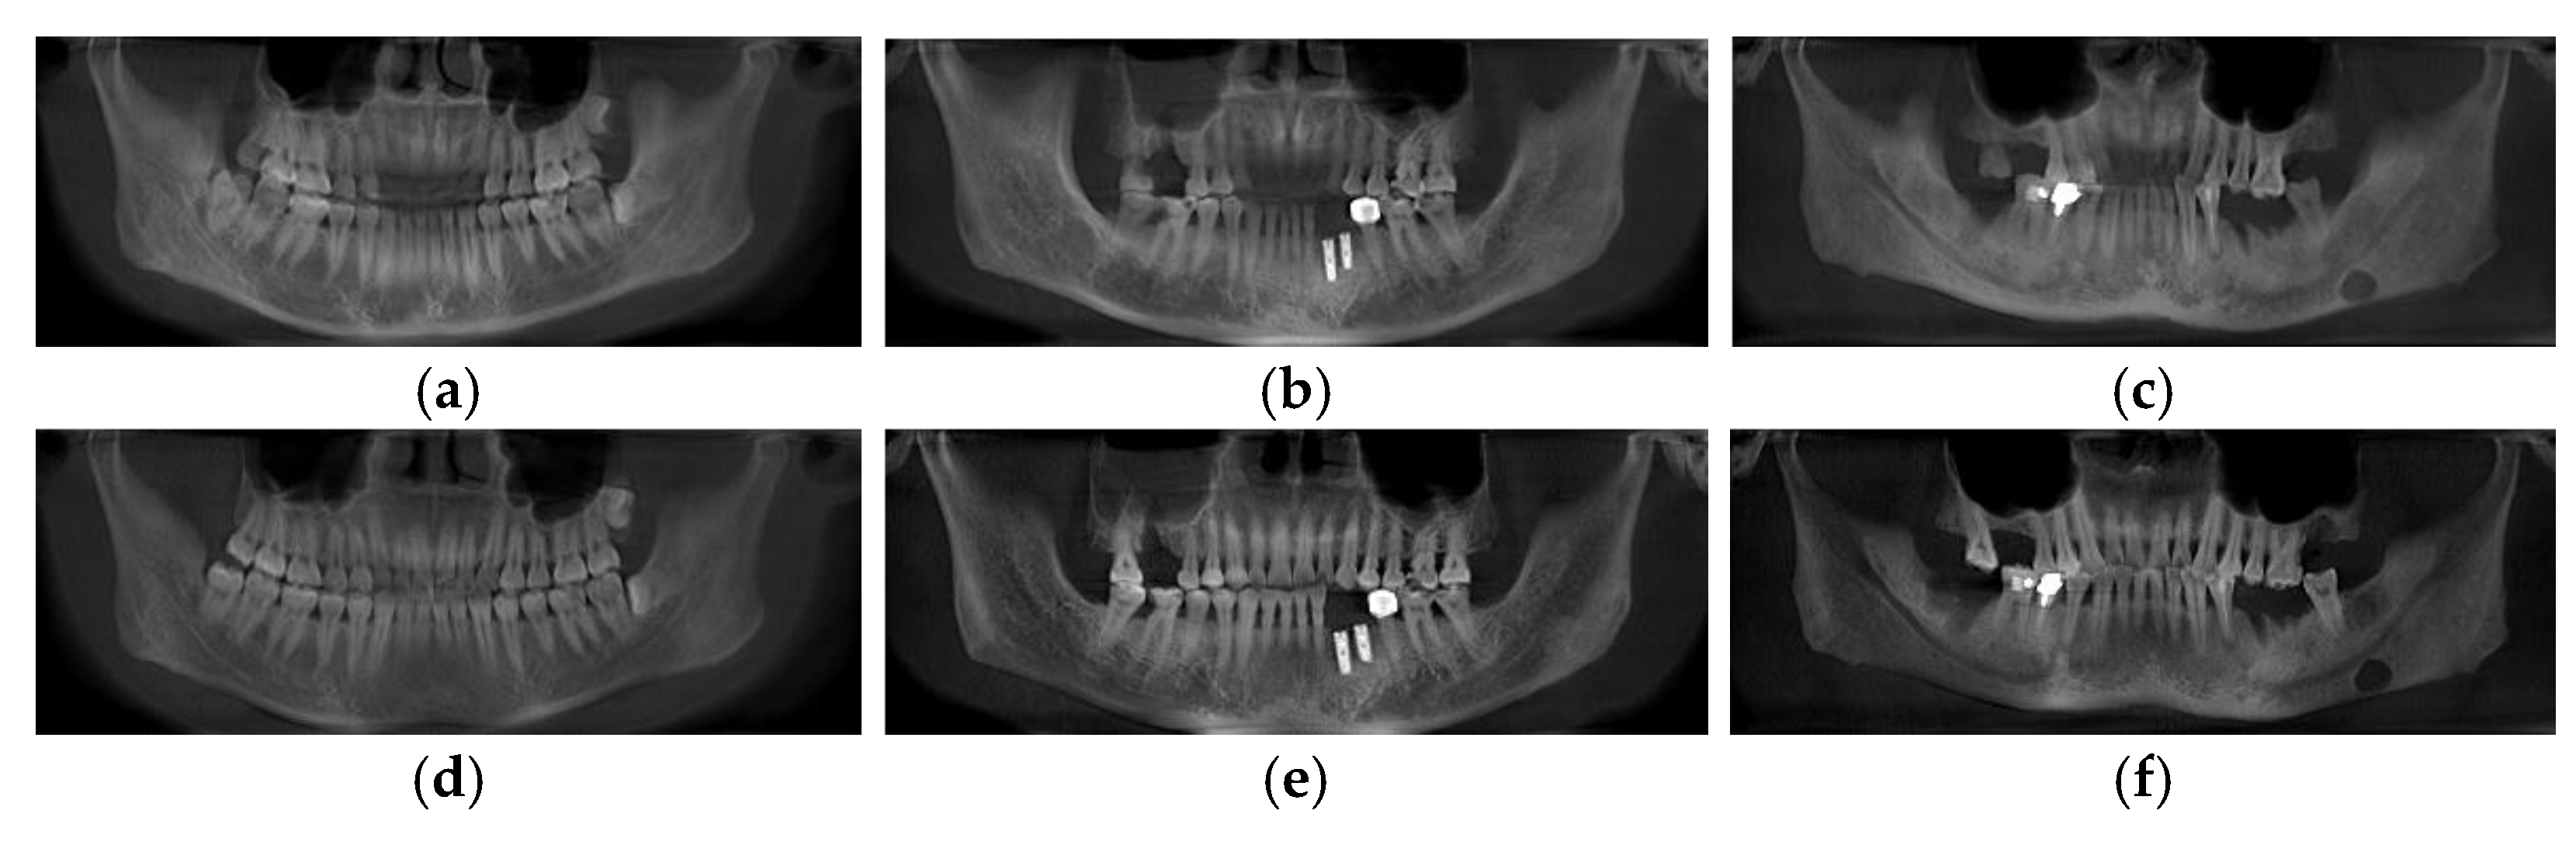

3.3. Different Types of Panoramic Image Effects